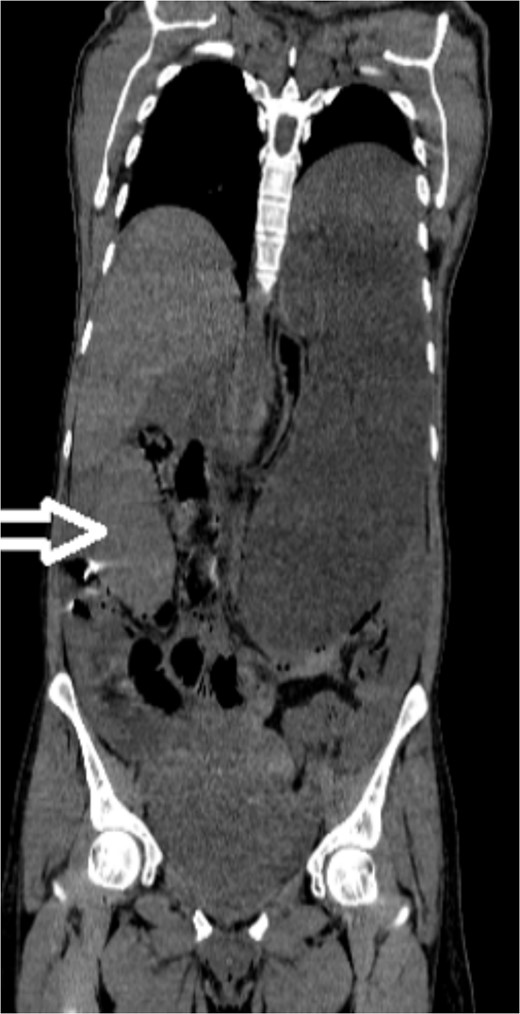

Upon admission to our hospital, the patient’s physical examination revealed hypotension (87/52 mmHg) and tachycardia (150 bpm), along with marked diffuse abdominal tenderness and guarding. Laboratory investigations indicated a hemoglobin level of 7.1 g/dl, a white blood cell count of 14.5 × 103 μl, and a platelet count of 202 × 103 μl. An abdominal CT scan without contrast showed an enlarged ectopic spleen measuring 18 cm in the right abdominal area, a distended stomach, a moderate volume of hemoperitoneum, and significant intra-abdominal fluid accumulation. CT findings are shown in Figs 1–3. Based on these findings, the patient was immediately transferred to the operating room.

Noncontrast axial CT scan of the abdominopelvic area showing a left-sided pelvic hematoma.